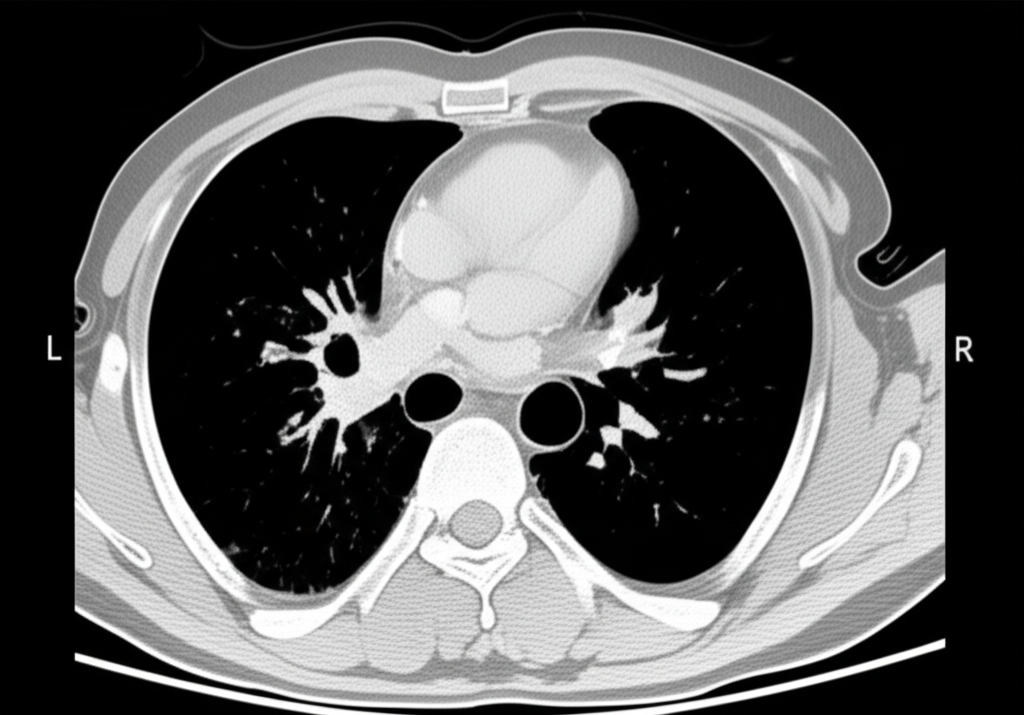

폐 CT는 폐 질환 진단에 매우 중요한 역할을 하는 영상 검사입니다. 흉부 X선 검사보다 훨씬 더 자세한 정보를 제공하여 폐암, 폐렴, 만성 폐쇄성 폐질환(COPD) 등 다양한 질환을 조기에 발견하고 정확하게 진단하는 데 도움을 줍니다. 건강 검진 시 폐 CT 검사를 고려하는 것은 건강한 삶을 유지하는 데 매우 현명한 선택입니다.

폐 CT로 알 수 있는 것은 폐암뿐만 아니라 폐렴, 결핵, 기관지확장증, 간질성 폐질환 등 다양한 폐 질환을 진단하는 데 유용합니다. 이러한 질환들은 호흡 곤란, 기침, 가래 등의 증상을 유발할 수 있으며, 심한 경우 생명을 위협할 수도 있습니다. 폐 CT 검사를 통해 이러한 질환들을 조기에 발견하고 적절한 치료를 받으면 질병의 진행을 늦추고 합병증을 예방할 수 있습니다.

폐 CT는 폐암의 크기, 위치, 림프절 전이 여부 등을 정확하게 파악하여 병기를 결정하는 데 중요한 역할을 합니다. 조기 폐암의 경우 수술적 절제를 통해 완치를 기대할 수 있으며, 폐 CT는 이러한 조기 진단에 결정적인 기여를 합니다.

폐 CT는 폐렴의 종류와 범위를 파악하고, 합병증 발생 여부를 확인하는 데 유용합니다. 특히 면역력이 약한 환자나 노인의 경우, 폐렴이 심각한 합병증으로 이어질 수 있으므로 폐 CT 검사를 통해 정확한 진단과 치료 계획을 수립하는 것이 중요합니다.

폐 CT는 COPD 환자의 폐기종 정도, 기관지 확장 여부, 폐렴 발생 여부 등을 평가하는 데 사용됩니다. 이를 통해 COPD의 진행 정도를 파악하고, 적절한 치료 계획을 수립하여 환자의 삶의 질을 향상시킬 수 있습니다.

폐 CT는 결핵 병변의 위치, 크기, 공동 형성 여부 등을 파악하는 데 유용합니다. 특히 흉부 X선 검사에서 발견하기 어려운 초기 결핵 병변을 발견하는 데 도움이 되며, 약물 치료 효과를 평가하는 데에도 활용됩니다.

폐 CT는 간질성 폐질환의 종류와 범위를 파악하고, 질병의 진행 정도를 평가하는 데 중요한 역할을 합니다. 간질성 폐질환은 폐 섬유화를 유발하여 호흡 곤란을 악화시킬 수 있으므로, 폐 CT 검사를 통해 조기에 진단하고 적절한 치료를 받는 것이 중요합니다.